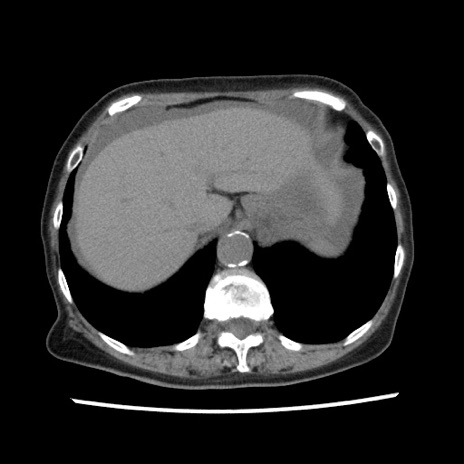

【症例】80歳代女性

【主訴】腹痛

【現病歴】8時間前から腹痛あり来院。

【既往歴】糖尿病、脂質異常症、子宮体癌にて子宮全摘術

【身体所見】意識清明・会話良好だが腹痛で苦悶様、全腹部にわたって反跳痛と圧痛あり

【データ】WBC 13600、CRP 0.14、LDH 224、CK 90